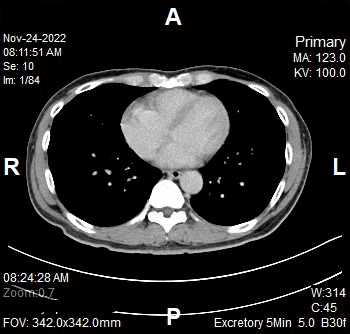

Excretory 5 Minutes

- Full abdomen

- Plan the Scan FOV (SFOV) box at topogram image

- Set the top line at the level of above diaphragm.

- Set the bottom line at the level of inferior ischial rami.

- Remind the patient before scanning as the breathing instruction will be given.

- Ensure the lateral line to cover patient’s body outline.

Reconstruction of Excretory 5 minutes

Series of Images Send to PACS

- Excretory 5min 5.0 B30f

- Excretory 5min 1.0 B20f